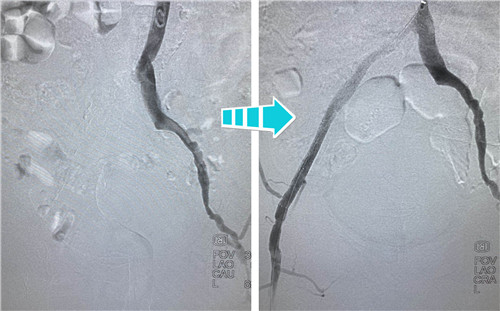

右側(cè)完全閉塞的髂血管順行開(kāi)通無(wú)果,但這也難不倒我們經(jīng)驗(yàn)豐富的鼓醫(yī)和石醫(yī)介入專(zhuān)家們,當(dāng)即決定由“順穿”改行“逆穿”。逆穿導(dǎo)絲難度大,技術(shù)要求高,十分考驗(yàn)術(shù)者的操作手法和預(yù)判,專(zhuān)家團(tuán)隊(duì)經(jīng)過(guò)內(nèi)膜下破膜逆行,一次性準(zhǔn)確對(duì)吻成功,同樣擴(kuò)張球囊、植入支架,血流瞬間恢復(fù)暢通。

術(shù)后,吳老先生的癥狀明顯改善,腿不疼了,走路也利索了,晚上終于可以睡個(gè)安穩(wěn)覺(jué)了。